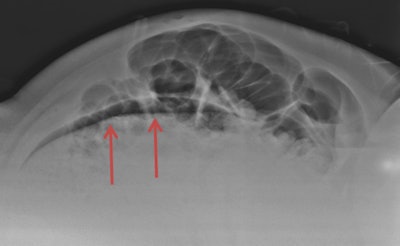

The imaging workup of patients with abdominal pain often starts with supine and upright abdominal x-rays and upright chest x-ray, and it is misinterpreting these images that is the main cause of diagnostic error in the emergency department, according to Pinto. He pointed to other factors contributing to missed diagnoses, such as a lack of relevant clinical information, inappropriate or insufficient x-rays, failure to perceive signs, and lack of knowledge.

CT is a valuable tool in nontraumatic abdominal emergencies, providing greater accuracy than ultrasound or plain x-ray for identifying pneumoperitoneum, as well as for evaluating bowel pathology, and retroperitoneal and bony abnormalities. Yet failure to continue to search for subsequent abnormalities after identifying an initial one (satisfaction of search), multitasking, and increased workload all may play an important role in missed diagnoses on CT, he explained.

His talk on errors in nontraumatic abdominal emergency will reveal a range of potential mistakes from the less severe to the more life-threatening, and he will provide tips on how to avoid the most common errors when diagnosing severity of disease and associated complications that could affect management and clinical outcome.

"Diagnostic radiology must aim for the complete detection -- and accurate diagnosis -- of all abnormalities. This depends entirely on perception and identification of specific image characteristics," he said.